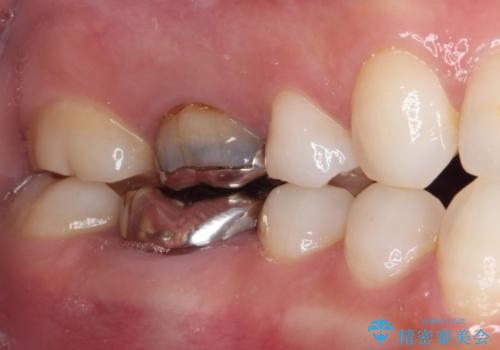

- 奥歯の銀歯が外れたことをきっかけに、全ての銀歯をセラミックに替えたいとのことで来院された患者様です。

第一大臼歯4本と、メタルインレーが装着されている2歯をセラミッククラウンならびにセラミックインレーにて補綴治療・修復治療を行うこととしました。

口腔内から、土台も含め銀歯がなくなったことでメタルフリーとなりました。